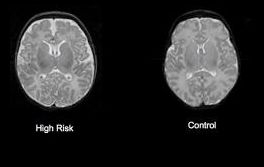

Liečbu schizofrénie komplikuje fakt, že sa prejaví zväčša až počas dospievania. V mozgu však príznaky vidno od doby krátko po narodení. V časopise American Journal of Psychiatry to predbežne online oznámil John Gilmore zo Severokarolínskej univerzity v Chapel Hill s kolegami. Schizofrénia je vážne mentálne ochorenie, ktoré celosvetove postihuje približne jedného zo sto ľudí. Vo väčšine prípadov sa príznaky prejavia až počas dospievania či dospelosti, najmä vo forme rôznych ilúzií a halucinácií. Dovtedy sa však táto choroba neraz rozvinie v takej miere, že je obtiažne liečiteľná.

Tím Johna Gilmorea ako prvý získal dôkazy, že anomálie spájané s rizikom schizofrénie možno odhaliť už v mozgoch niekoľkotýždňových bábätiek. "Dovoľuje nám to začať premýšľať o včasnej identifikácii detí ohrozených schizofréniou a o tom, či jestvujú určité veci, ktoré by sme mohli urobiť v ich veľmi skorom veku, aby sme toto ohrozenie znížili," povedal John Gilmore. S kolegami vyšetril ultrazvukom a zobrazovaním pomocou magnetickej rezonancie vývoj mozgu 26 bábätiek, ktoré sa narodili matkám s diagnostikovanou schizofréniou. Blízky príbuzný s touto chorobou zvyšuje riziko z jedna ku sto na jedna ku desať. Výskum odhalil, že vysokorizikoví chlapci mali väčšie mozgy a väčšie bočné komory, priestory v mozgu vyplnené kvapalinou, ako bábätká neschizofrenických matiek. U dievčat sa nič také nezistilo. To zodpovedá skutočnosti, že schizofrénia viac postihuje mužov a máva u nich tiež vážnejší priebeh. Väčší mozog novorodencov súvisi aj s autizmom, no na druhej strane automaticky neznamená prepuknutie schizofrénie či autizmu.